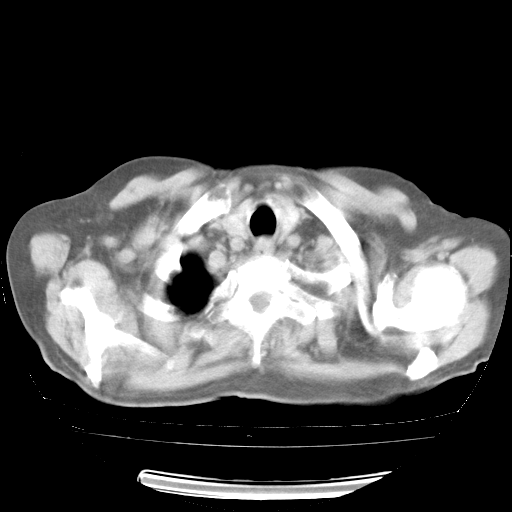

4月28日肺部CT